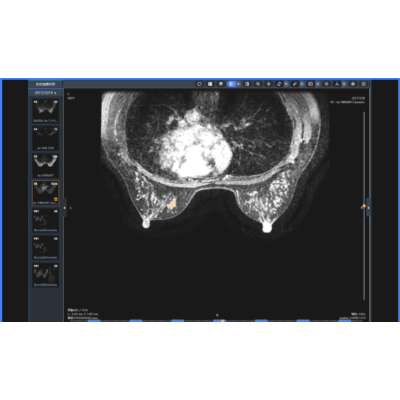

乳腺病变辅助诊断

应用乳腺MR检查T1、T2、DCE、DWI序列数据,智能化完成乳腺腺体结构类型确定、乳腺病变识别检出与分割定位、乳腺病变MR BI-RADS分型;辅助诊断原位癌、浸润性癌、导管内乳头状瘤、纤维腺瘤、叶状肿瘤、乳腺炎、腺病等乳腺疾病;自动生成结构化报告,输出早期强化率(EER)、TIC曲线、ADC数值等多维度参考信息,帮助医生提高诊断效率。